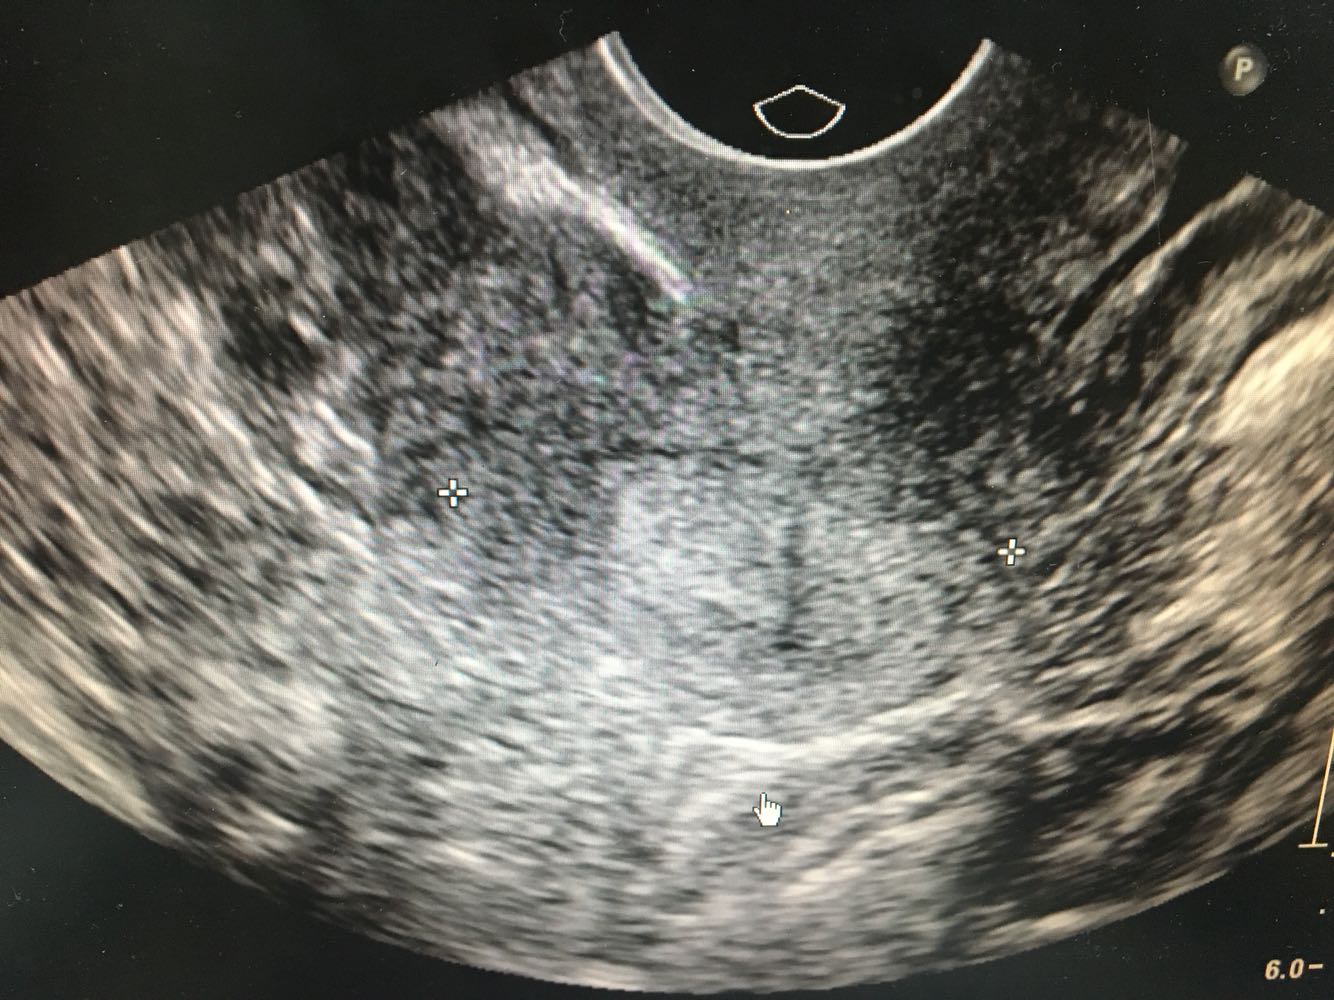

4、查体:外阴:(-)。阴道:通畅,阴道壁粘膜充血,散在出血点。子宫:屏气用力时可见子宫颈及阴道前壁脱出超过处女膜缘<1cm,子宫颈可见轻度柱状上皮外移,子宫体水平位,萎缩,活动良好,无压痛。附件:双侧附件未及明显包块及压痛。     5、辅检:【腹部B超】双肾囊肿;【妇科B超】子宫未见异常,双卵巢未探及